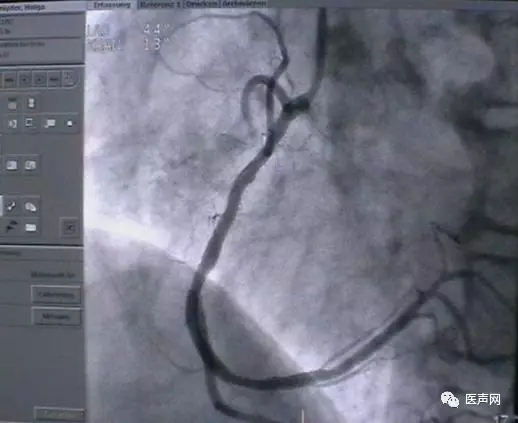

病例3:LAD中段90%狭窄

操作过程:JL4导引导管同轴性不好,支撑力不够,直接支架术(direct stent)有阻力,改用EBU 导引导管---植入TAXCOR 3.0×18mm DES.说明:导引导管的重要性。下图所示: